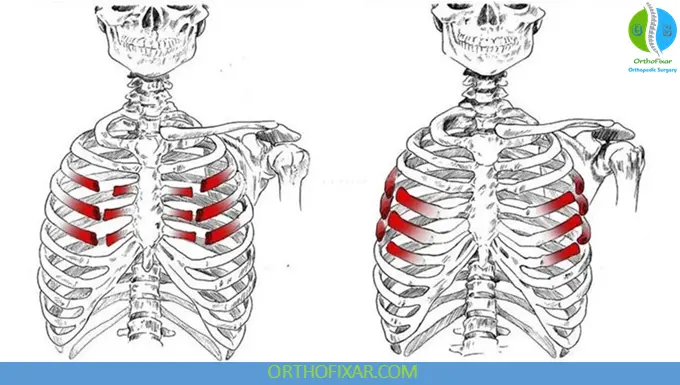

Special pattern: Flail Chest

- Defined as ≥3 consecutive ribs fractured in ≥2 places

- Creates a free-floating segment of the chest wall

- Occurs in up to 13% of chest wall trauma cases

- Associated with significant morbidity and respiratory compromise